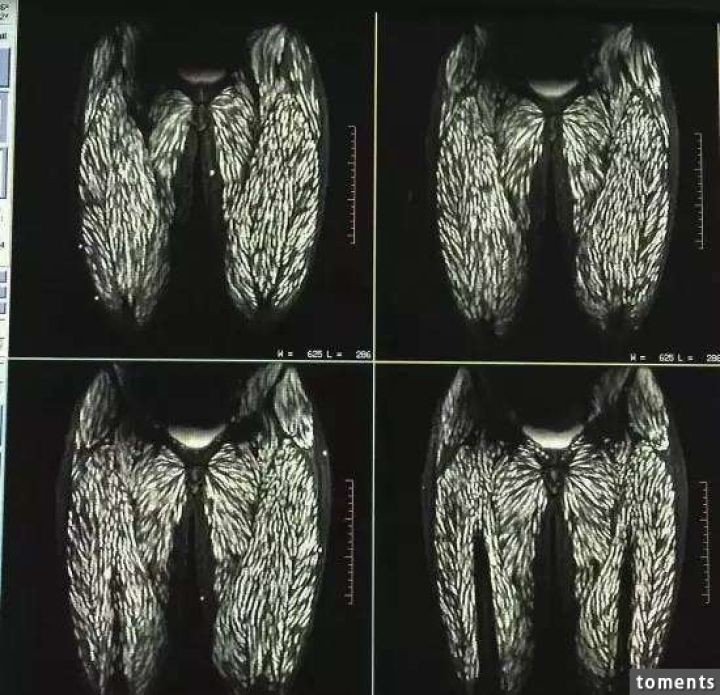

病院では頭部MRIと全身CTスキャンが行われたが、その検査結果は専門家さえも驚く衝撃的なものだった。それもそのはず、女性の全身はすでに無数の寄生虫に侵されており、大脳や顔面の筋肉にさえも感染が見られるひどい有様だったからだ。

医師の話では、女性の体内の寄生虫の一部はすでに死に、石灰化しており、全身の痛み以外に眼球突出や網膜出血といった症状も見られたとのこと。治療はすぐに行われたものの、一部の寄生虫は体外に排出されず、女性には後遺症が現れる可能性も否めないという。